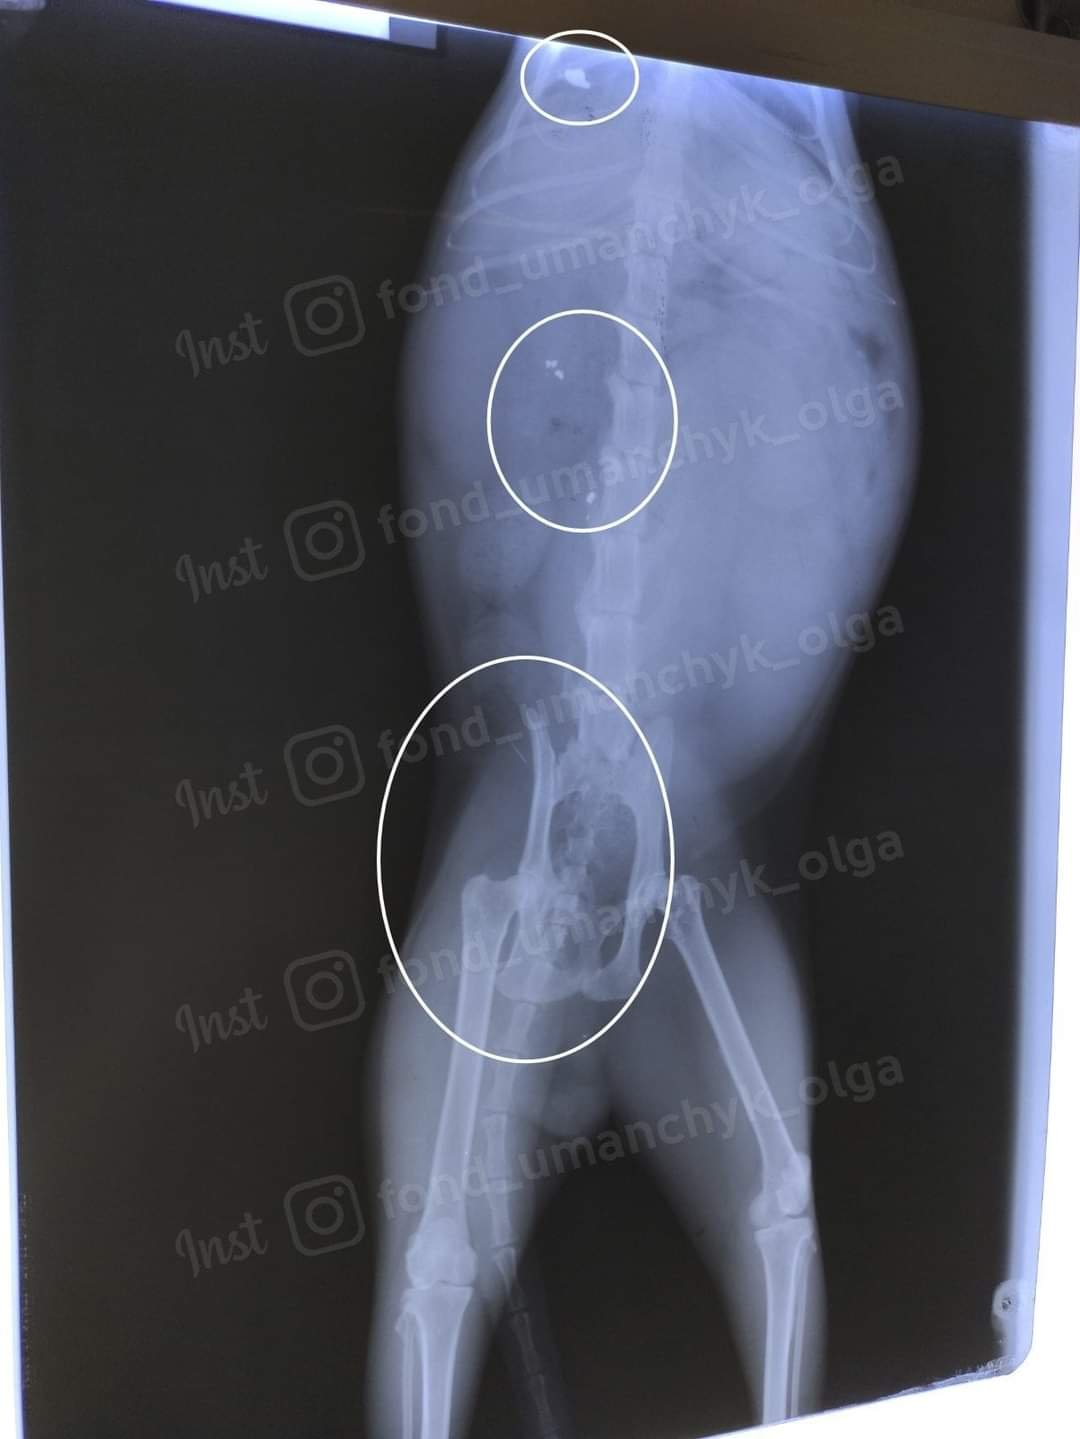

"Долг на сегодня больше 3 700 грн (повторное обследование, УЗИ, взятие мочи через прокол, консультация невролога, повторный рентген). Собрано 0 грн. Несчастного Хортона сбила машина, искусали и порвали коты, его пинали люди под подъездом. На улице он мучительно погибал! Котик не может сам полностью опорожнить мочевой пузырь. Из клиники его выписали, как здорового. Увы, пришлось снова обращаться к врачам. Невролог обследовал котика. На рентгене нашли осколки пули и один из них в позвоночнике! А это значит, что проблема может быть не только в изуродованных машиной костях таза, но и в том, что в котика стреляли. Хортона нужно отдавливать (сцеживать мочу) два раза в сутки. Это могут делать только в ветклинике. Пока лечение выписано на месяц. Если не будет улучшений, то скорее всего - операция", - рассказала Ольга.